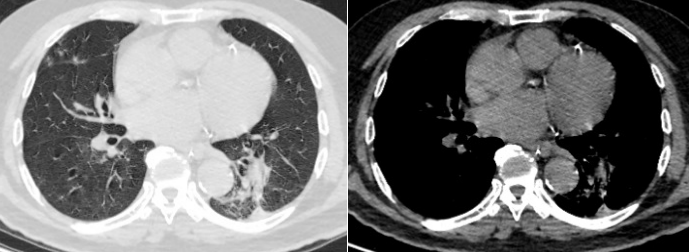

胸部CT(2025-04-23):右肺中上叶渗出,部分实变。右主支气管及右肺上叶支气管内多发黏液栓形成;两肺多发索条影;纵隔内稍大淋巴结;主动脉、冠状动脉硬化(图1)

1  患者入院胸部CT2025-04-23)